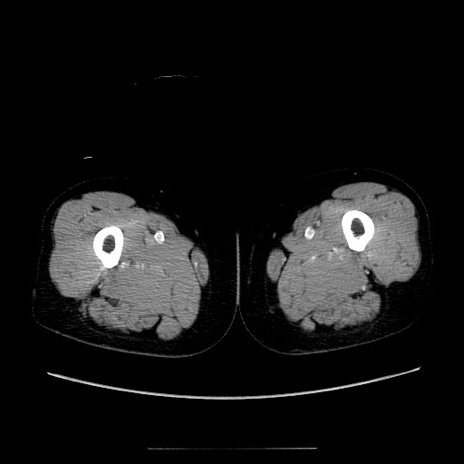

症例5(横断像)

【症例】70歳代女性

【主訴】お腹が張る

【現病歴】1週間くらい前から腹部膨満の自覚あり。昨日夜から増悪したため、本日救急外来受診。

【身体所見】意識清明、BT 36.5℃、BP 165/106mmHg、HR 80bpm、SpO2 98%、腹部:膨満、軟、自発痛・圧痛なし、触診にて不快感あり、腸蠕動音:減弱

【データ】WBC 12600、CRP 1.04